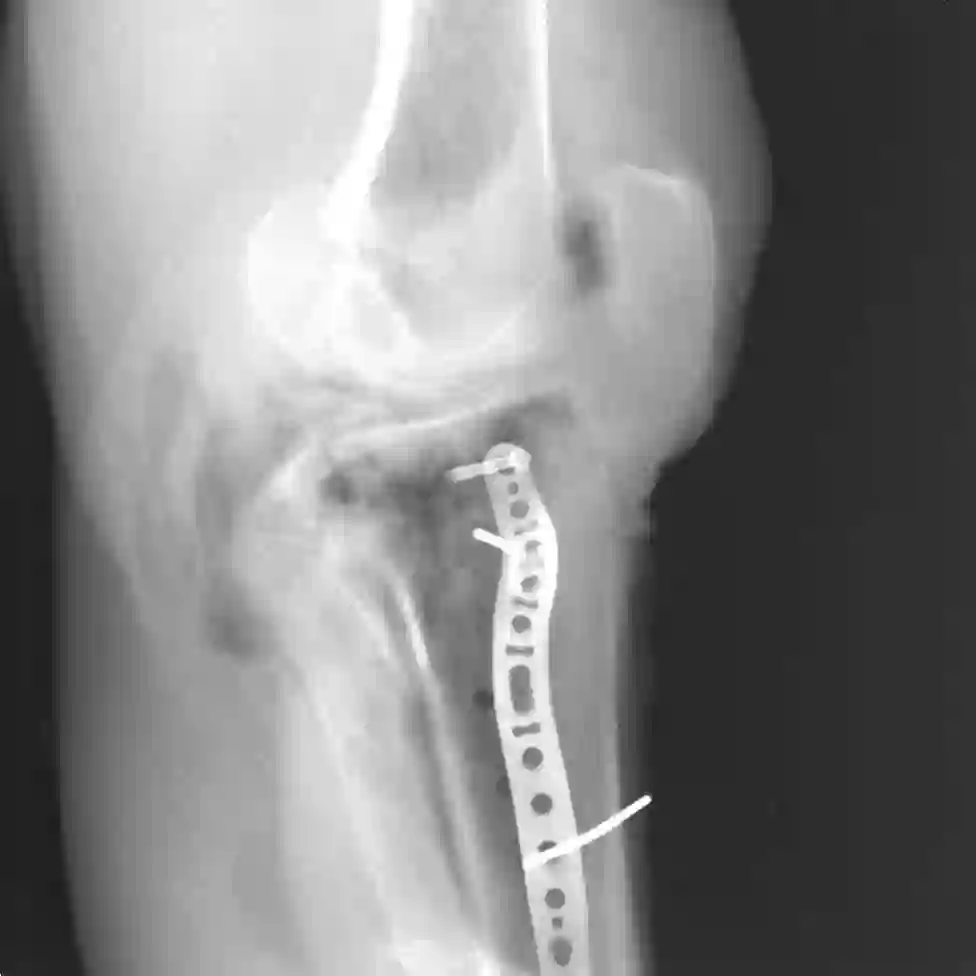

Metal implants that are inserted into the patient's body during trauma interventions cause heavy artifacts in 3D X-ray acquisitions. Metal Artifact Reduction (MAR) methods, whose first step is always a segmentation of the present metal objects, try to remove these artifacts. Thereby, the segmentation is a crucial task which has strong influence on the MAR's outcome. This study proposes and evaluates a learning-based patch-wise segmentation network and a newly proposed Consistency Check as post-processing step. The combination of the learned segmentation and Consistency Check reaches a high segmentation performance with an average IoU score of 0.924 on the test set. Furthermore, the Consistency Check proves the ability to significantly reduce false positive segmentations whilst simultaneously ensuring consistent segmentations.